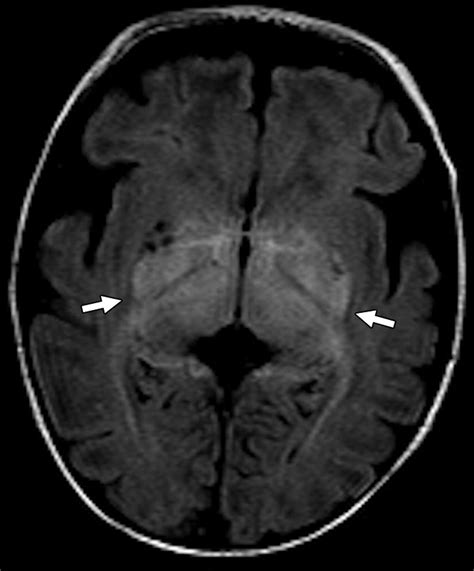

Moreover, advancements in neuroimaging, such as high-resolution fMRI, are allowing researchers to visualize the activity within the individual layers of the LGN in living humans. This technology provides unprecedented insight into how visual processing is affected by neurodegenerative diseases and helps map the pathways involved in visual processing disorders.

• lateral geniculate nucleus mri